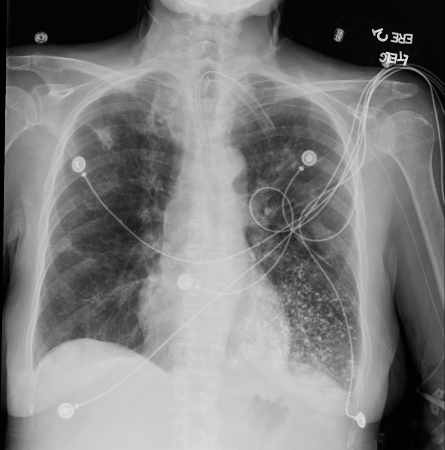

[Figure caption and citation for the preceding image starts]: A. Portable upright chest x-ray before aspiration; B. Chest x-ray 1 hour after aspiration, showing bilateral diffuse alveolar infiltrates, worse at the bases on the right sideFrom the collection of Dr Henri Colt [Citation ends].

Be aware that chest x-ray changes may only be seen if acute aspiration has led to aspiration pneumonitis or pneumonia. However, a normal chest x-ray does not exclude aspiration pneumonia, with some studies demonstrating a significant number of cases where thoracic CT scans identified aspiration pneumonia in patients who did not demonstrate findings on chest x-ray.[44] Bear in mind that aspiration pneumonitis and pneumonia can also co-exist.

Also note that the pattern of chest x-ray changes varies depending on the positioning of the patient when they aspirate, and the mechanism of aspiration.

Look for patchy, bilateral airspace consolidations with a perihilar and basilar distribution following aspiration.[35]

Chest x-ray findings of aspiration pneumonitis usually develop within 2 hours of aspiration and sometimes resolve quickly. However, opacities due to aspiration pneumonia can develop days later and can take weeks to resolve.